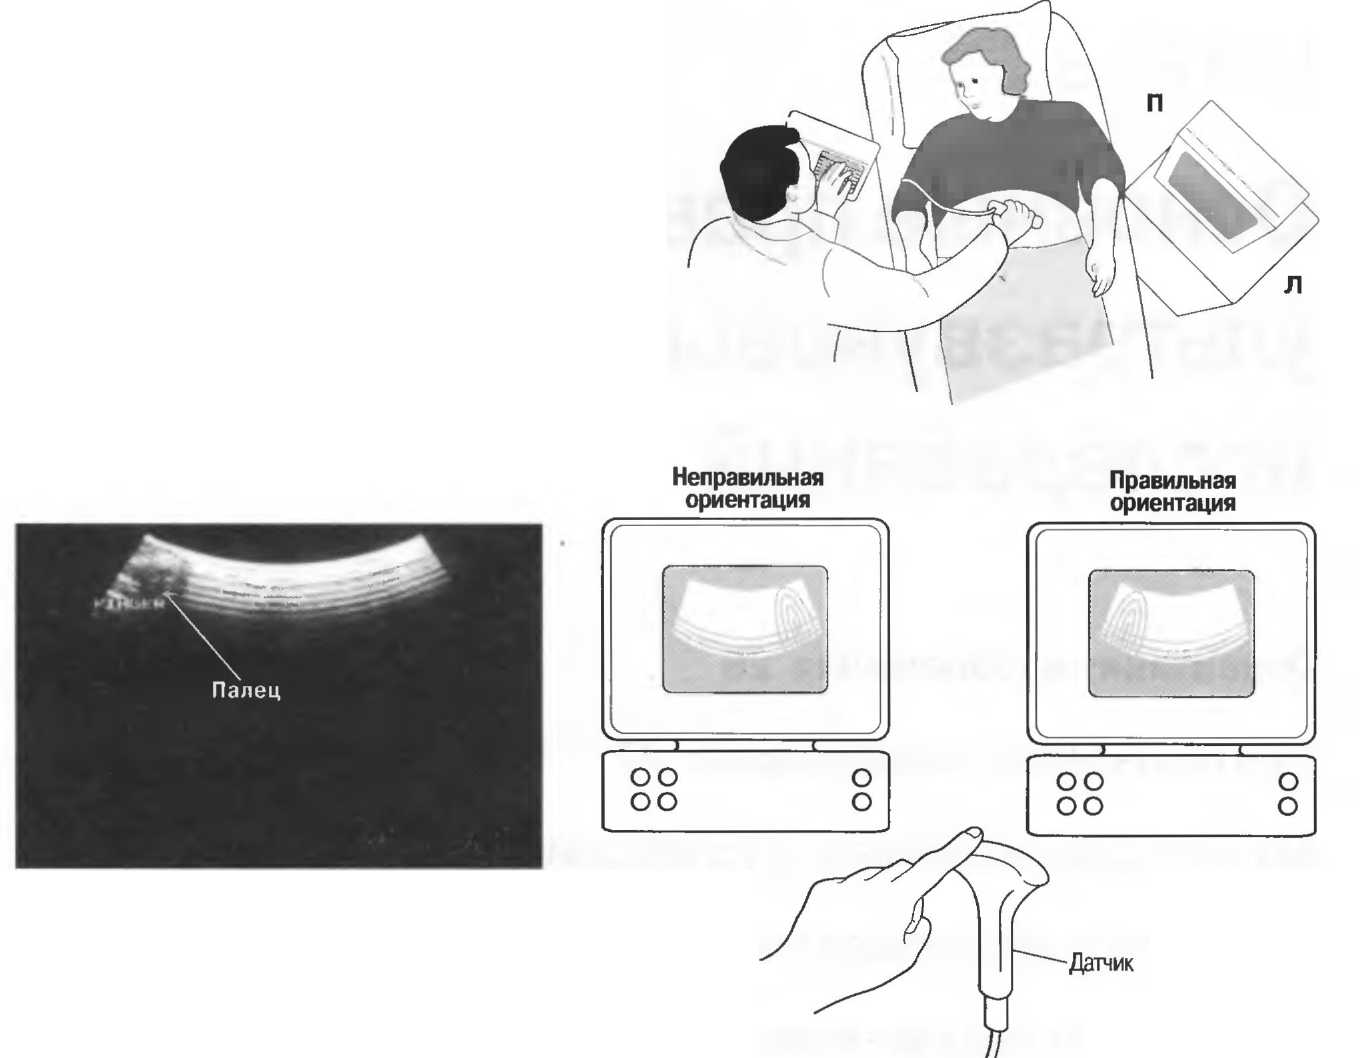

При поперечном сканировании изображение на экране монитора может перевернуться таким образом, что левая сторона пациента окажется с правой стороны экрана. Несмотря на то что на датчике имеется индикатор положения, важно перед исследованием визуально проверить соответствие стороны датчика соответствующей стороне получаемого изображения. Лучше всего это сделать, поместив палец на один конец датчика и посмотрев, с какой стороны экрана получится его изображение. При неправильной ориентации нужно развернуть датчик на 180" и проверить снова (рис. 8а). На продольных срезах голова пациента должна определяться на экране слева, а ноги—справа.

Рис.8а. Палец на датчике должен давать изображение на соответствующей стороне экрана Если стороны не совпадают, поверните датчик на 180°.

Рис.8б. Два аксиальных среза головки плода, развернутые на 180°. Перед проведением исследования ориентация изображения на экране должна быть проверена, как показано на рис. 8а.